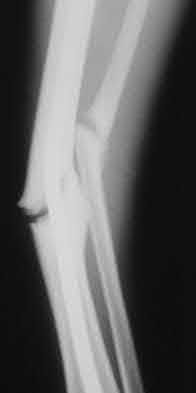

1. # A 32-year-old male sustains the injury shown in Figure A and undergoes treatment as shown in Figure B. Following placement of this implant, what is the best technique to confirm it is not too proud proximally?

2. # A 35-year-old woman is involved in a head-on collision while driving. Initial radiographs are shown in Figures 8a and 8b. Injury to what vessel increases the risk for osteonecrosis of the injured bone?

5. Artery of the tarsal sinus Corrent answer: 4

The patient has a Hawkins type III talar neck fracture-dislocation with a risk of osteonecrosis ranging from 69% to 100%. Anatomic studies have shown that the artery of the tarsal canal supplies the lateral two thirds of the talar body.

The other vessels listed provide no significant contribution to the talus.